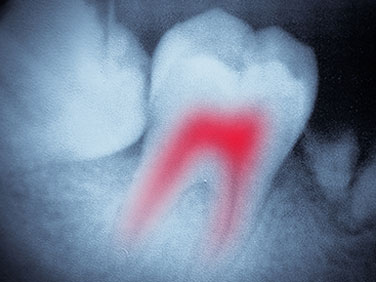

Root Canal X-Ray

Root Canals

We all dread hearing the words “root canal.” However, this is usually based on a misunderstanding and exaggeration. A root canal is actually a relatively pain-free procedure that stops the pain of an infected tooth. In other words, the infection, not the root canal is the primary cause of the excruciating pain. Putting off a dental procedure is never a good idea. You’ll likely suffer more in the long run. If you’ve been told you need a root canal, don’t wait another day. Come on in and schedule an appointment with Dr. Jack.